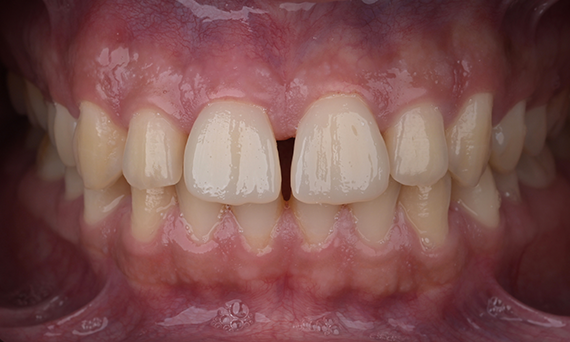

Initial situation of the patient:

The patient presented with increasing temperature sensitivity at her six-year molars. The anamnesis did not reveal any evidence of a drug-associated or disease-associated enamel malformation. The mother’s pregnancy was without complications. Clinical examination revealed extensive substance loss and hypomineralised enamel encompassing the entire clinical crowns of teeth 16 and 26. Furthermore, the left central incisor and both mandibular first molars were affected by hypomineralisations. Tooth 21 had no cavitation and showed no hypersensitivity. The lower first molars had small cavitations with hypersensitivity. Based on these findings diagnosis was molar-incisor-hypomineralisation (MIH). According to the MIH-Treatment-Need-Index [Bekes & Steffen 2016] teeth 16 and 26 were assigned to Score 4c requiring full crown coverage. Tooth 21 was assigned to Score 1 and was left as it was at the request of the mother and the patient herself. Teeth 36 and 46 were assigned Score 4b and were restored with direct composite restorations.

At this point, the maxillary molars were not yet fully erupted. Therefore, these teeth were initially restored with direct composite restorations to await complete tooth eruption. At the age of 11, tooth 16 and 26 had erupted completely allowing for full crown restorations.